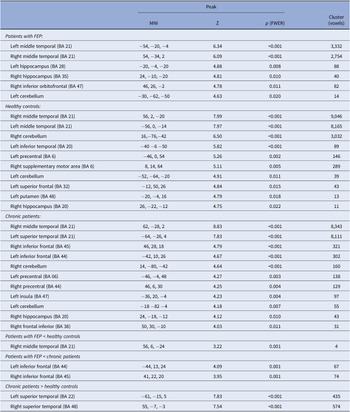

Patients with FEP showed activation during the emotional word task in the bilateral middle temporal (BA 21), bilateral hippocampus (left, BA 28; right, BA 35), right inferior orbitofrontal (BA 47), and left cerebellum (Table 3 and Figure 1).

Table 3. Regions showing activation when hearing of emotional versus neutral words in patients with FEP, healthy controls, and chronic patients.

Note: Additionally differences in functional activation between FEP versus healthy controls and FEP versus chronic patients were showed. Statistical threshold: familywise error rate (FWER) < 0.05 with 10-voxel cluster extent, except for the between-group comparisons (uncorrected p < 0.001).

Abbreviations: BA, Brodmann area; FEP: first-episode psychosis; FWER, familywise error rate; MNI, Montreal neurological institute.

HCs showed a similar pattern of activation, including the bilateral middle temporal (BA 21), left inferior temporal (BA 20), bilateral cerebellum, left precentral (BA 6), right supplementary motor area (BA 6), left superior frontal (BA 32), left putamen (BA 48), and right hippocampus (BA 20) (see Table 3 and Figure 1).

Chronic patients mainly activated the right middle temporal (BA 21), left superior temporal (BA 21), bilateral inferior frontal (left, BA 44; right, BA 45), bilateral cerebellum, bilateral precentral (left, BA 06; right, BA 44), left insula (BA 47), right hippocampus (BA 20), and right frontal inferior gyrus (BA 38) (see Table 3 and Figure 1).

Compared with control subjects, FEP patients did not show any differences in activation, with FWER <0.05. However, using a liberal threshold (uncorrected p < 0.001), they showed hypoactivation in the right temporal lobe (BA 21). Similarly, the inferior frontal gyrus (bilateral) showed a significant reduction in activation in FEP patients when compared with chronic patients (uncorrected p < 0.001) (BA 44, BA 45) (Table 3).